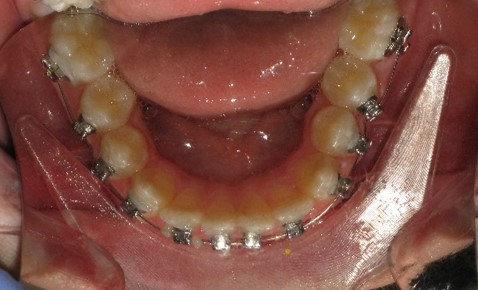

После дистализации боковых сегментов на верхней челюсти и правильной постановки клыков в зубной ряд проведена фиксация аппарата на нижний зубной ряд и дальнейшая коррекция окклюзии проводится по стандартному протоколу, т.е. нормализация формы зубных рядов на верхней и нижней челюсти с правильной постановкой зубов по торку в боковых и во фронтальном отделах, что дает реализация программы, заложенная в пассивной самолигирующей брекет- системе NexStep Pro 0.22. (рис.8)

Рис.8. Этап контроля торка на верхней челюсти и фиксация аппарата на нижней челюсти для проведения этапа нивелирования.